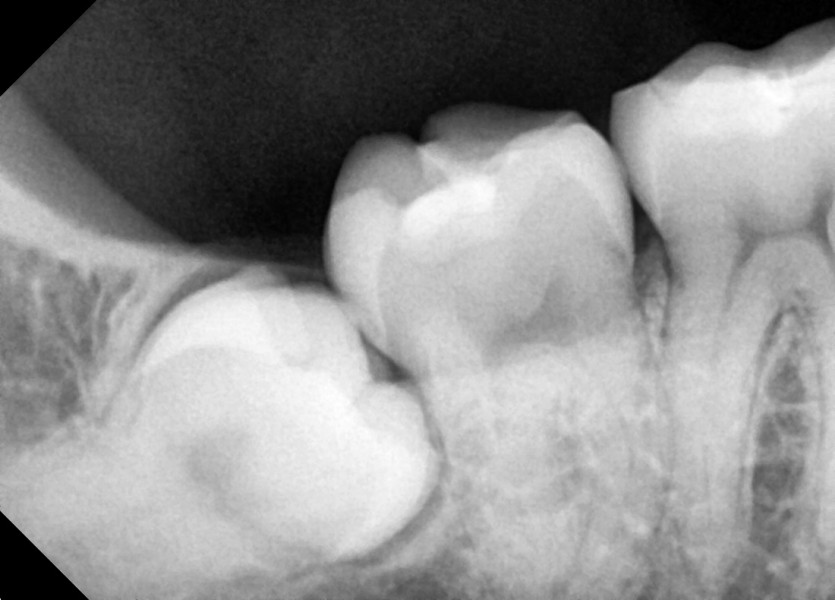

#48 사랑니 발치

구강 외과 전문의가 당일 발치했습니다.